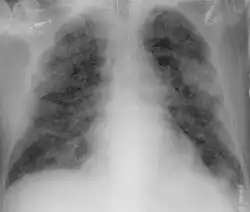

Chest X-ray showing COVID‑19 pneumonia

Chest CT scans may be helpful to diagnose COVID‑19 in individuals with a high clinical suspicion of infection but are not recommended for routine screening.[175][187] Bilateral multilobar ground-glass opacities with a peripheral, asymmetric, and posterior distribution are common in early infection.[175][188] Subpleural dominance, crazy paving (lobular septal thickening with variable alveolar filling), and consolidation may appear as the disease progresses.[175][189] Characteristic imaging features on chest radiographs and computed tomography (CT) of people who are symptomatic include asymmetric peripheral ground-glass opacities without pleural effusions.[190]

Many groups have created COVID‑19 datasets that include imagery such as the Italian Radiological Society which has compiled an international online database of imaging findings for confirmed cases.[191] Due to overlap with other infections such as adenovirus, imaging without confirmation by rRT-PCR is of limited specificity in identifying COVID‑19.[190] A large study in China compared chest CT results to PCR and demonstrated that though imaging is less specific for the infection, it is faster and more sensitive.[174]